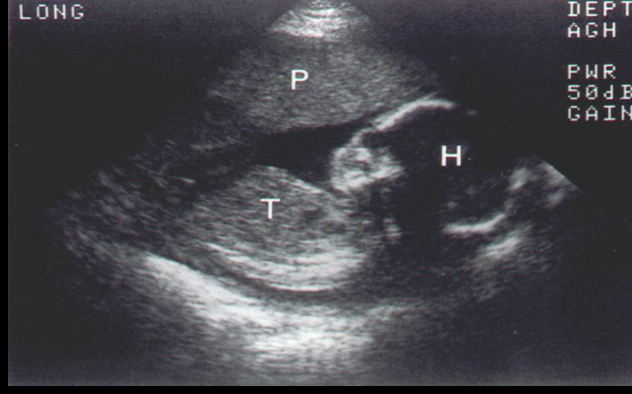

Uses sound waves reflect tissues safe for preggo and kids real time images of moving structures

Ultrasound

term image

Ultrasounds

Tumors mostly in ovaries, derived from all 3 germ layers, can grow teeth hair muscle cell and epithelium

Dermoid cyst